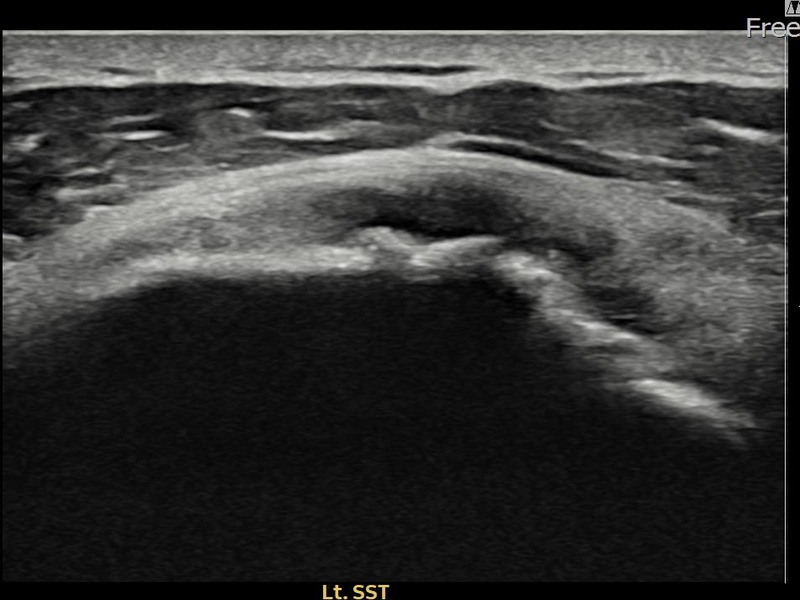

김ㅇㅇ님 · 좌측 극상근건 광범위 부분파열

좌측 어깨 광범위 파열로 수술을 권유받았으나 비수술 치료를 원해 내원하셨습니다. 초음파 검사에서 극상근건 전층에 걸친 광범위 부분파열이 확인되었으며, 어깨인대 축소봉합술 후 구조적 안정화와 기능 회복이 이루어졌습니다.